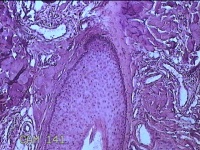

头部肿物

性别

男

年龄

21岁

临床诊断

头皮肿物

一般病史

发现头部结节10余年,无明显疼痛及不适。

标本名称

头部结节

大体所见

灰白暗红色带皮肤样结节1.5x1.3x0.3cm一个,切开结节呈实性,切面灰白粉红色,质软。